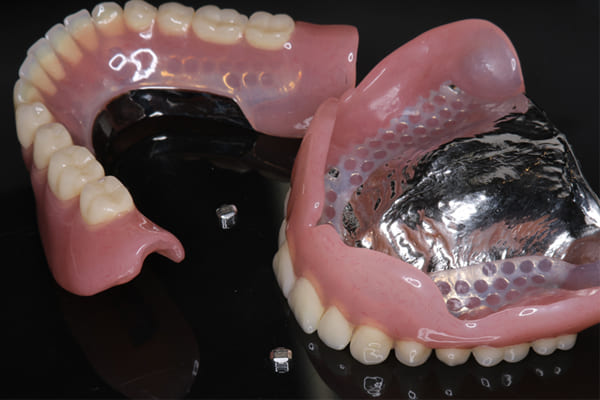

治療前の入れ歯の奥歯は、治療後の義歯と比較しても分かるように、歯が削れ平らになった状態です。

これにより奥歯のかみ合わせは低くなり、前歯のみが強くあたり、かみ合わせにより上の前歯大きな負担がかかっていたことにより、上の前歯が折れたことが考えられます。

精密な型どりは、通常保険治療では使用しない、この患者様だけに合った型を取るトレーを作製、また寸法変化の最も少ない精密なシリコンを用いてお口の中を精密に限りなく再現する型どりの方法で型をお取りしました。

完成前に適合や見た目のチェックでは、咬む力で義歯がたわみ、残りの歯に負担がかからないよう、見えない内側は、金属を用い、強度を増し、また金属のため薄くすることで違和感をなくす設計とし、完成前に試し合わせを行い、装着感、審美性を確認しました。

治療用入れ歯は患者様とご相談し、早急にお痛みをとり、お食事ができることをご希望されていたため、歯を抜くと同時に仮の入れ歯が入りお食事をされた後のお写真です。直ちに、お痛みを取り除き、お食事ができるような治療計画としました。

精密義歯は、歯をぬいたあと歯肉が治ってから、精密な入れ歯を作製しました。治療中も、仮の入れ歯があるため、普段の生活に支障がなく、また仮の入れ歯を実際使ってのご意見、ご希望(バネが気になる)をお聞きした上で、精密な義歯に、ご希望を反映し作製しました。